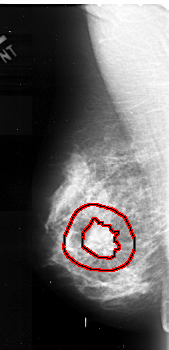

FILE: A_1104_1.LEFT_CC.OVERLAY

TOTAL_ABNORMALITIES 1

ABNORMALITY 1

LESION_TYPE MASS SHAPE IRREGULAR MARGINS SPICULATED

ASSESSMENT 5

SUBTLETY 5

PATHOLOGY MALIGNANT

TOTAL_OUTLINES 2

BOUNDARY

CORE